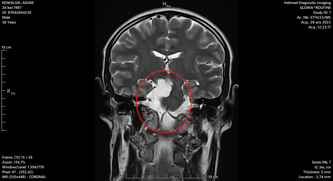

Adam ma NOWOTWÓR MÓZGU I INNYCH CZĘŚCI OŚRODKOWEGO UKŁADU NERWOWEGO - w dodatku bardzo rzadki i niespotykany... Jest to perlak kąta mostowo-możdzkowego z penetracją do dołu międzykonarowego i podstawy czaszki oraz jamy Meckela. Adamowi grozi m.in. wodogłowie, porażenie nerwów odpowiedzialnych za funkcje życiowe, deformacja pnia mózgu, upośledzenie... Tak naprawdę grozi mu wszystko, bo ogromny guz wnika do każdej szczeliny w jego głowie i nadal rośnie ! Czas jest tutaj na wagę złota...